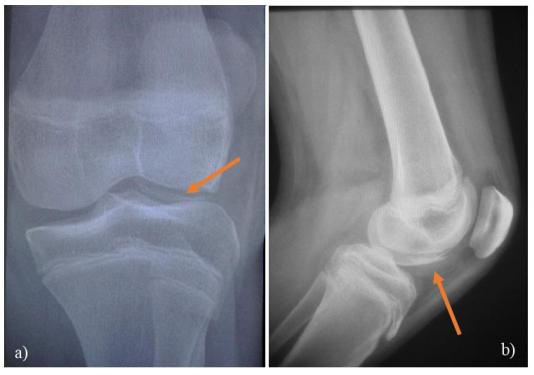

Se trata de un paciente de sexo femenino de 12 años, estudiante, procedente de Montevideo, sin antecedentes personales patológicos a destacar, deportista amateur. En setiembre del 2016 mientras practicaba gimnasia rítmica sufre un traumatismo indirecto de rodilla izquierda quedando con dolor, edema y limitación funcional a dicho nivel. Consultando en la emergencia del Centro Hospitalario Pereira Rossell (C.H.P.R.), donde se indica analgesia vía oral y reposo deportivo por tres semanas. Luego de la primera consulta la paciente reconsulta en tres oportunidades en emergencia por gonalgia y episodios de derrame articular, donde se indicó reposos deportivo y analgésicos. En junio del 2017 la paciente consulta en policlínica de traumatología del C.H.P.R., destacándose de la anamnesis la presencia de dolor intermitente de tipo mecánico, en especial cuando practicaba actividad deportiva, presentando episodios de derrame articular recurrente, incluso limitando el perímetro de marcha sin dolor a 500 metros, sin nuevos episodios de luxación patelo-femoral. Del examen físico se destaca, discreto derrame articular en rodilla izquierda, dolor leve a la flexo-extensión máxima, aumento de la excursión externa de la rótula en comparación con la contralateral, no signo de la J caracterizado por el encarrilamiento defectuso de la patela durante su discursión en la troclea, rodilla estable, sin signos meniscales, piel sana, sin alteraciones neurovasculares. En la consulta se solicitaron rx en forma urgente de frente y perfil de rodilla (Figura 1), que muestra la presencia de un fragmento osteocondral caracterizado por una imagen de doble contorno a nivel del cóndilo femoral externo. Se completó la valoración imagenológica con una resonancia nuclear magnética (RNM) (Figura 2).

Figura 1. a) Rx de frente de rodilla izquierda de nuestro paciente donde se aprecia un cuerpo libre intrarticular correspondiente a un fragmento osteocondral del cóndilo femoral externo (flecha). b) Rx de perfil de la misma rodilla donde observa una imagen en doble contorno (flecha).